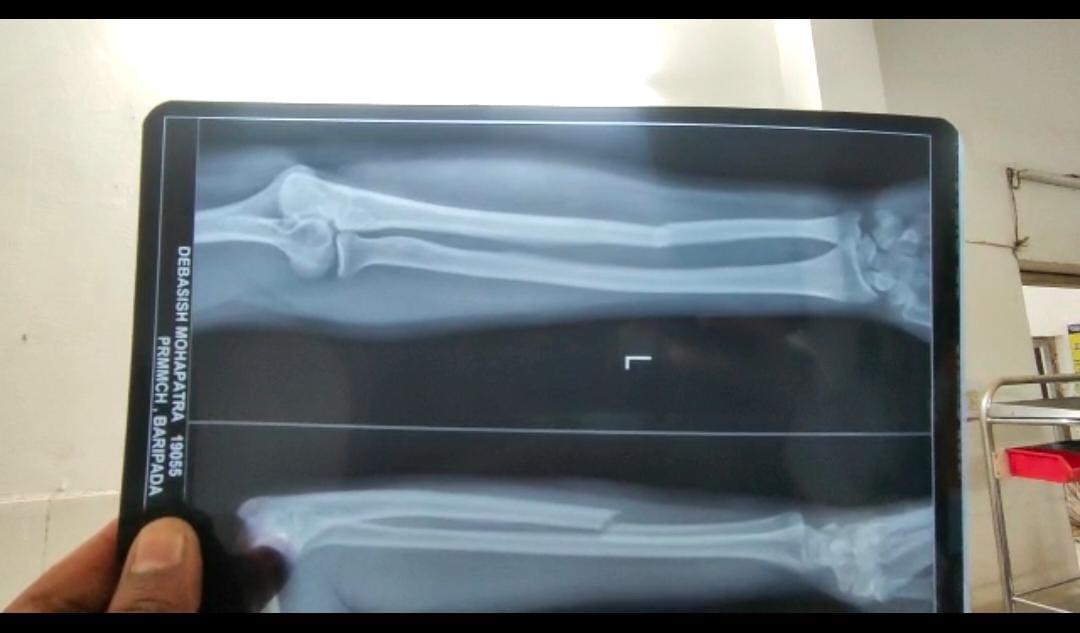

पीड़ितों का कहना है कि रिव्यू मीटिंग के दौरान मंत्री किसी बात को लेकर बहुत उग्र हो गए और उन्होंने अंदर से दरवाजा बंद कर दोनों अफसरों पर कुर्सी से हमला कर दिया. इस हमले में देबाशीष महापात्रा का हाथ टूट गया है. जबकि अश्विनी कुमार मलिक को चोटें आई है. दोनों अधिकारियों को बारीपदा के पीआरएम मेडिकल कॉलेज में भर्ती कराया गया है.

घायल अधिकारियों में से एक, देबाशीष महापात्र ने कहा, "मंत्री ने पहले हमें यह कहते हुए डांटा कि हमने प्रोटोकॉल का उल्लंघन किया है. हमने उन्हें समझाने की कोशिश की कि अगर हम आदर्श आचार संहिता के समय फाइलों के साथ उनके कार्यालय जाते तो यह अनुचित होता. आगामी पंचायत चुनावों के कारण राज्य में आचार संहिता लागू है. लेकिन, वह नाराज हो गए और हमें मारना शुरू कर दिए."